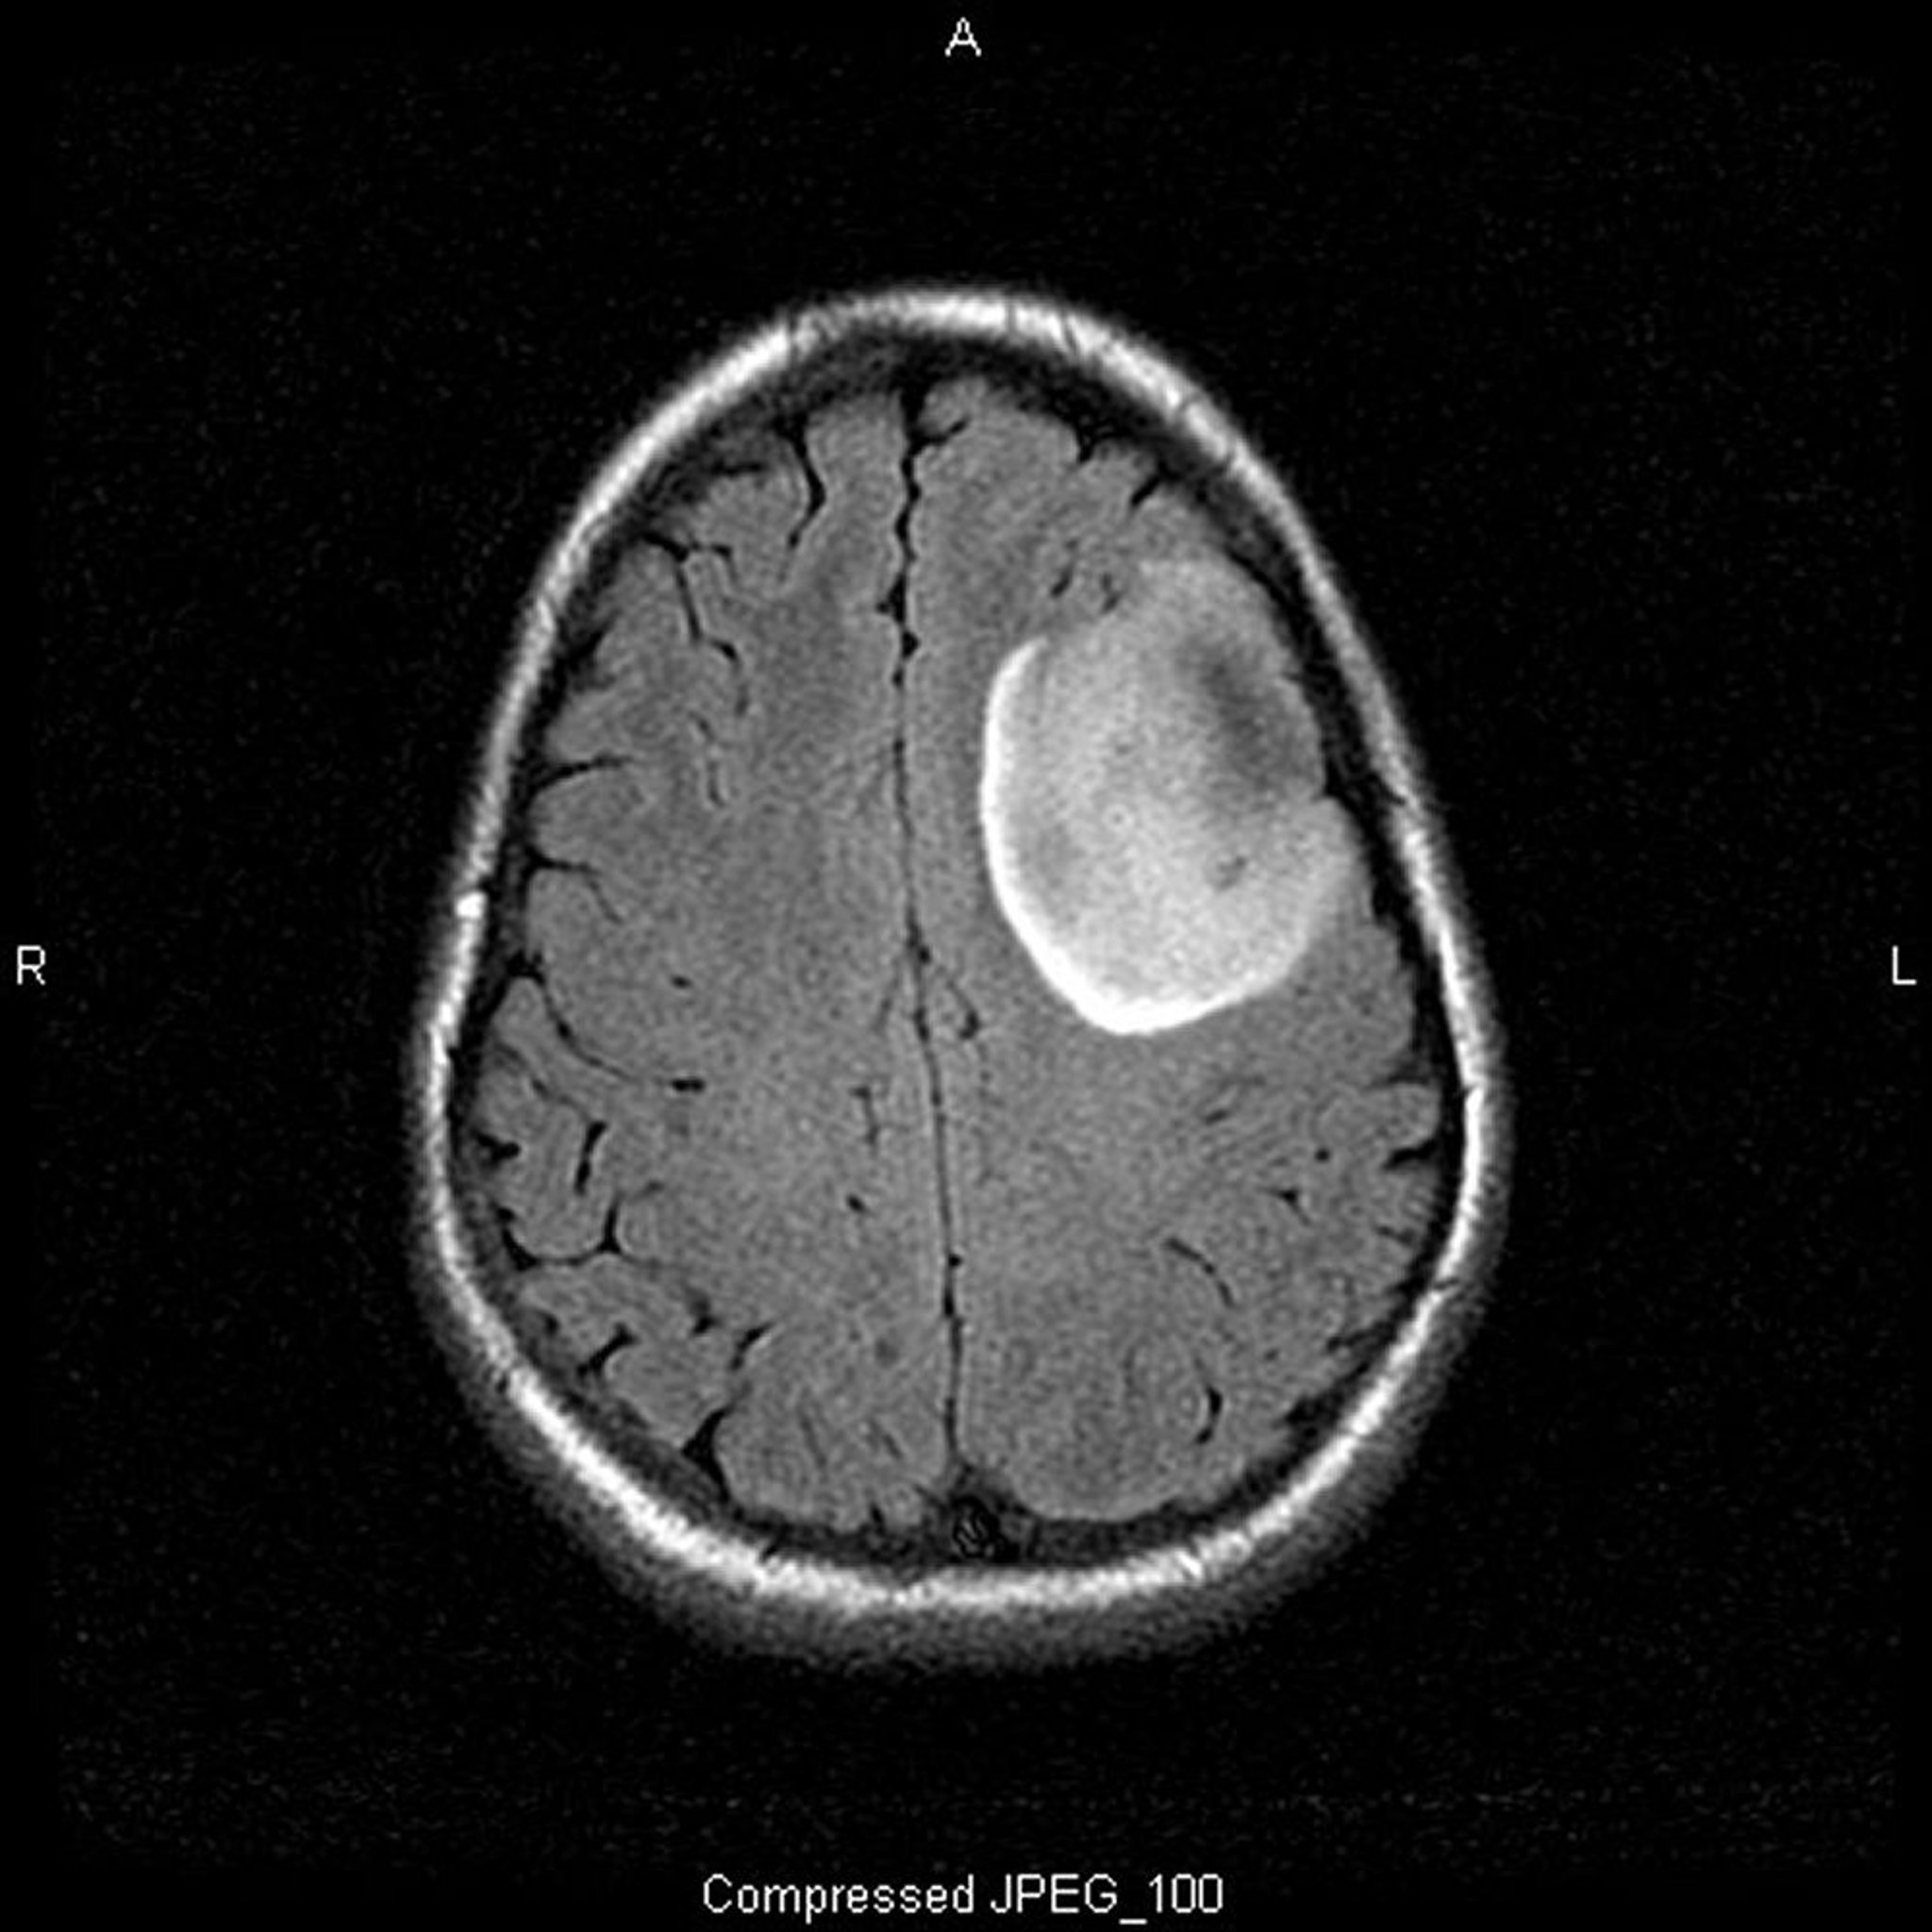

Олигодендроглиома, низкодифференцированная

Т2-FLAIR (восстановление с инверсией затухания жидкости) взвешенное МРТ-сканирование показывает наличие сигнала белого поля, который может свидетельствовать про развитие опухолевого образования или отека. Левый фронтальный сигнал сильно ограничен, что указывает на опухолевое образование. Использование контраста не усиливает его. Низкозлокачественная олигодендроглиома II степени.

Image courtesy of William R. Shapiro, MD.